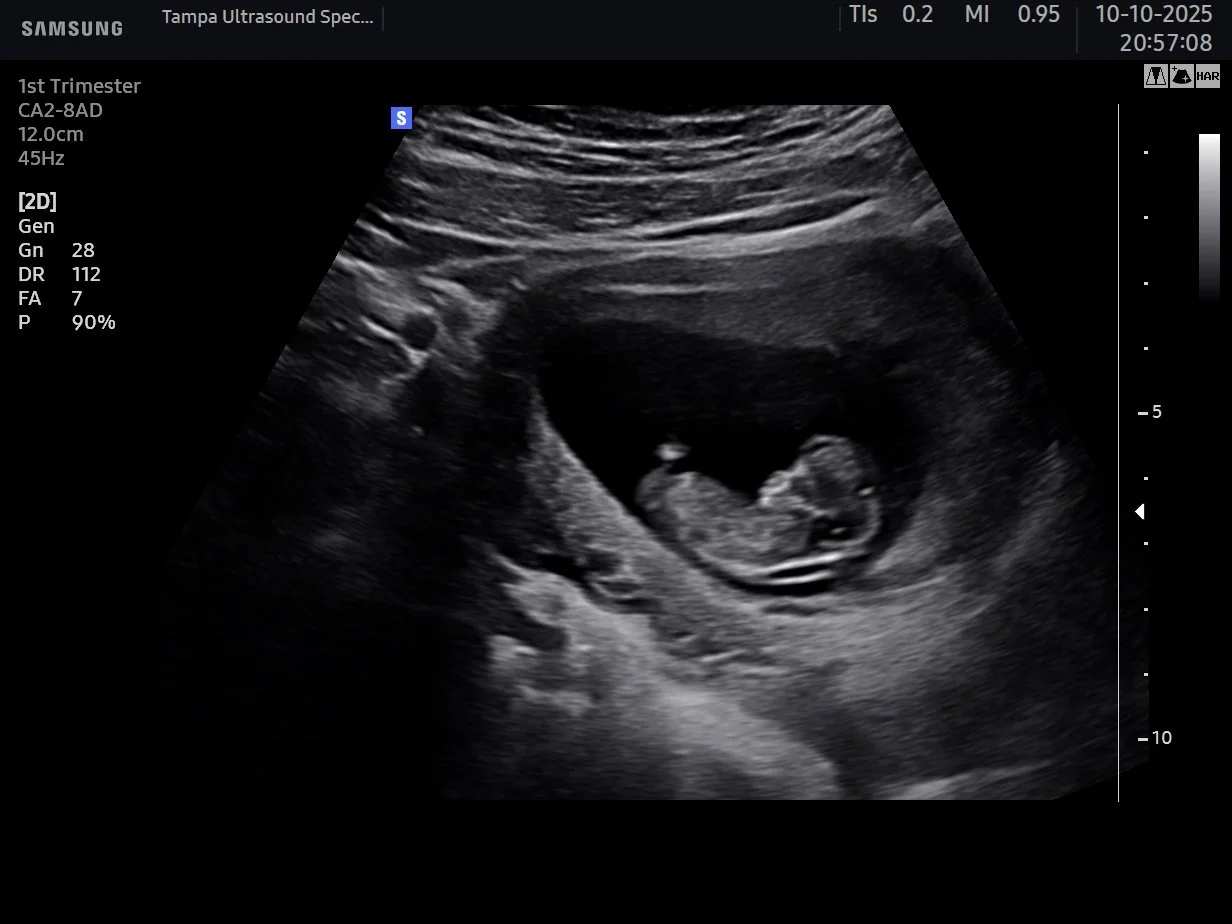

Weeks 6 to 14

First Look -- 2D

See your baby and hear their heartbeat for the very first time. 2D imaging gives the clearest view at this early stage.

First Look Ultrasound Tampa -- Early Pregnancy 2D Sessions (Weeks 6 to 14)

See your baby and hear their heartbeat for the very first time. Perfect for early pregnancy reassurance and bonding. Available from 6 weeks. No referral needed. No insurance required. From $80.

Can I get a 3D/4D ultrasound in the first trimester in Tampa? Yes. Tampa Ultrasound Specialist offers first trimester ultrasound sessions starting from 6 weeks. While 2D imaging gives the clearest view in early pregnancy, 3D images are possible and our sonographer will guide you on what to expect at your stage.